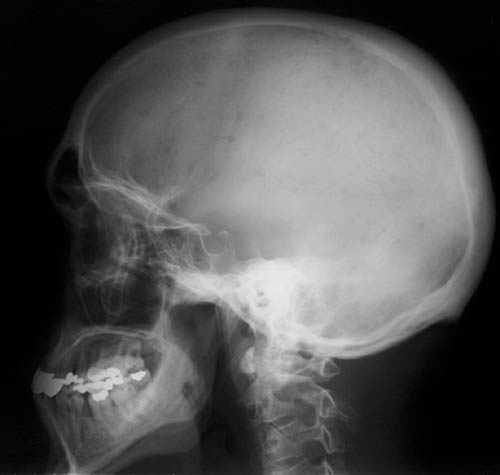

There are numerous small round, lucent "punched out" lytic lesions in the skull of a patient with multiple myeloma and a monoclonal gammopathy.